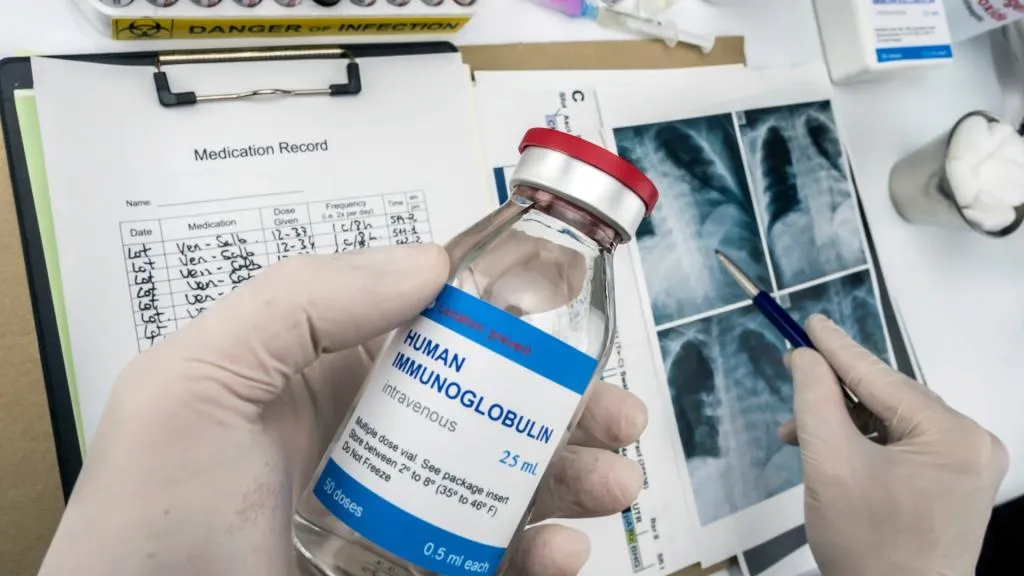

Hemodiafiltração exige ajuste de dose dos medicamentos? O que um caso de vancomicina pode nos ensinar

Hemodiafiltração exige ajuste de dose dos medicamentos? O que um caso de vancomicina pode nos ensinar

A hemodiafiltração pode aumentar significativamente a depuração de diversos medicamentos, levando a subdosagem quando usamos protocolos baseados em hemodiálise convencional. Entender a farmacocinética da droga e a prescrição da HDF é essencial para evitar falha terapêutica e ajustar corretamente as doses.